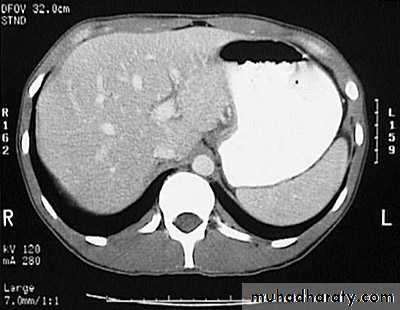

Secondary metastasis in the liver

Multiple rounded hypo density areas of different density , shape & different size .

Pattern of enhancement is either uniform , target or bulls eye pattern .

Hepato megaly .

Secondary metastasis within the liver

CT Scane